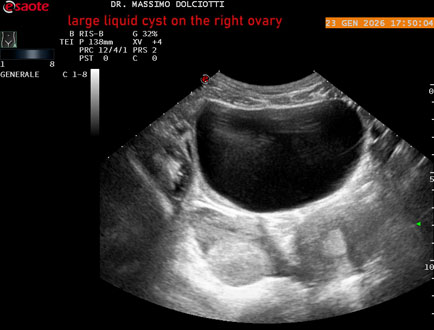

Età Paziente: F 29 anni

Motivazione dell'esame: dolore al lato destro della pelvi in portarice di cisti liquida all'ovaio destro.

Commento all'esame: le immagini ed il video documentano, in sede pelvica, grande formazione anecogena, delle dimensioni di 110 x 60 mm, priva di vascolarizzazione, da ricondurre a grande cisti liquida dell'ovaio destro.

Conclusioni: grande cisti liquida all'ovaio destro (large fluid cyst on the right ovary).